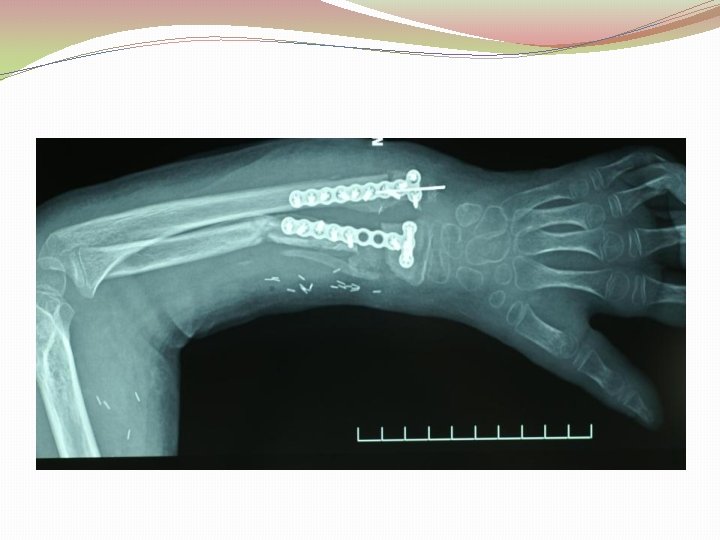

Ķirurģiska ārstēšana Osteomielīta pacientiem jāveic radikāls debridement ķirurģiski, kas ietver visu procesā iesaistīto audu rezekciju: �Mīksto audu rētas rezekcija �Cīpslu kalcinātu rezekcija �Distantu sekvestru rezekcija �Kaula rezekcija līdz vizuāli veseliem audiem – readzama punktveida asiņošana ´Paprika sign’. Bogdan Maciuceanu, Lucian Jiga, Alexandru Nistor, Jenel Marian Pastrascu, Mihail Ionac Chronic Osteomyelitis of Long Bones Timisoaral Medical Jornal, 2005

Ķirurģiska ārstēšana Veiksmīgas ķirurģiskas ārstēšanas stūrakmens ir mirušas telpas ‘Dead space’ aizpildīšana, kas izveidojas pēc debridemet veikšanas Brad Parsons, Elton Strauss, Surgical management of chronic osteomyelitis, The American Journal of Surgery 188 (Suppl to July 2004) 57 S– 66 S

Debridement Os konstrukciju evakuācija Biopsija un mikrobioloģija Dobuma slēgšana Antibakteriāla terapija Stabilizācija (Ārējā fiksācijas aparāts) Maina vai apstiprina antibakteriālo terapiju Mīksto audu rekonstrukcija 6 nedēļas antibakteriāla terapija (pēc debridement) Pseidartroze Konsolidācija Atkārtot ārstēšanu Luca Lazzarini, Jan T. Mader, Joson H. Calhaun Osteomielitis in Long Bone, The journal of bone&joint surgery, Volume 86 A, nr 10, 2004